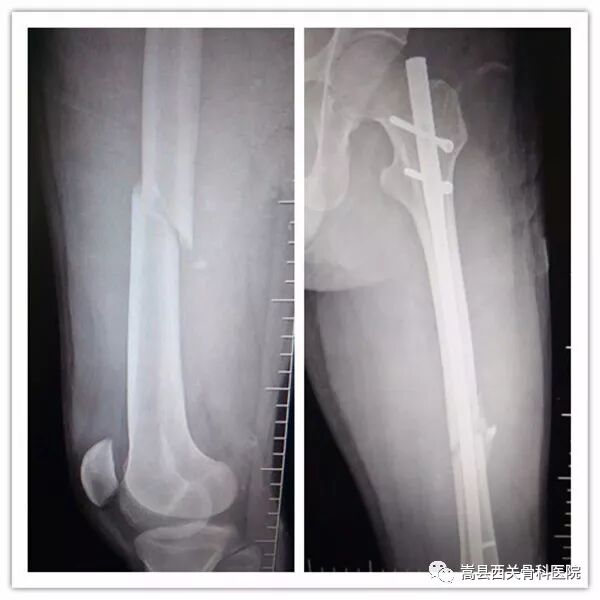

(图为患者术前术后DR片)

麻醉后患者取仰卧位,先行透视下骨折闭合复位,再于臀部做一长为3.0CM左右的微小切口,经过开口、扩髓、透视等一系列操作后插入一枚合适的带锁髓内钉,并分别进行远近端交锁,对骨折进行牢固内固定。

该技术骨折处不切开,创伤小、切口小、术中出血少,基本上没有并发症,病人术后第二天即可拄拐下床行走,骨折恢复快。